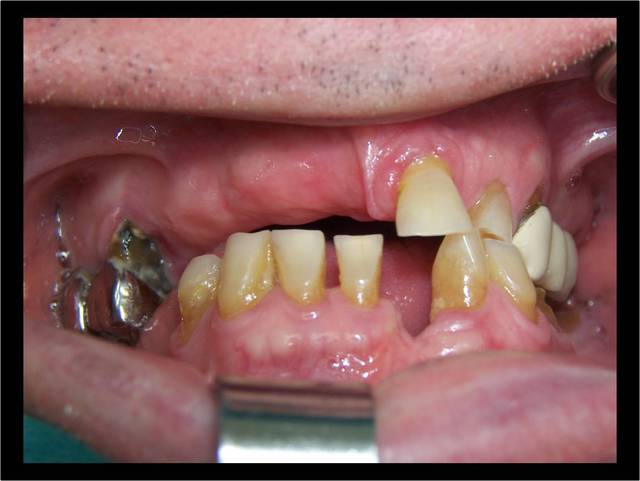

Vous regardez un cas de mci et ne voyez que l’implant sur 9 (je ne parle pas des derniers qui n’ont que quelques jours) qui posé il y a 4 ans lors d’un sinus lift latéral ne va pas bien, et de 2 (8) qu’un 3ème année pourrait enlever.

Aujourd’hui le protocole serait scanner, discussion avec mes associés paro et ortho, et probablement exo, Mci sans sinus lift.

Le patient a eu un traitement paro suivi d’une contention ortho. Une option était exo 11 21 25 et bridge 15 à 25, mais 13 14 15 étaient latéro déviées cela se devine sur la photo que Noah a reprise.

Et même en ayant posé les implants en palatin secteur 1, je serais sans doute obligé de faire quelque chose pour 43 44 45